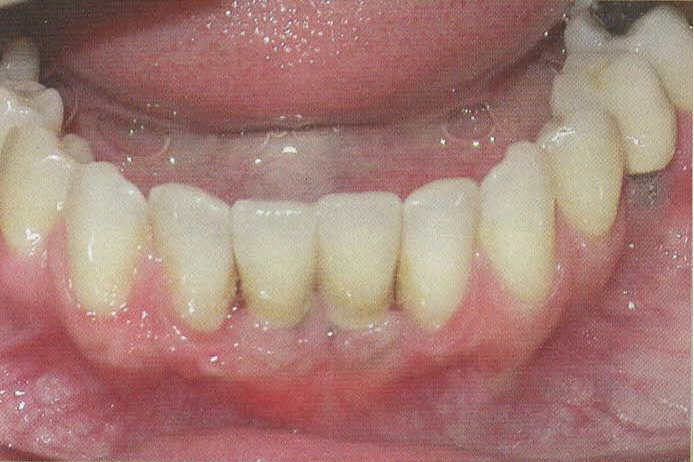

CERAMICHE SU IMPIANTI

Per l'esecuzione delle impronte vengono usati materiali di prima qualità perchè la precisione delle impronte facilita la costruzione del manufatto e questo è un passaggio fondamentale per la buona riuscita della protesi.

In questo studio vengono eseguite ceramiche di ultima generazione quali la zirconia ceramizzata, le ceramiche estetiche in disilicato senza trascurare le tradizionali metalceramiche. Il disilicato è un materiale altamente estestico che conferisce alla corona protesica un aspetto naturale e con questo materiale si possono creare manufatti con uno spessore molto ridotto.